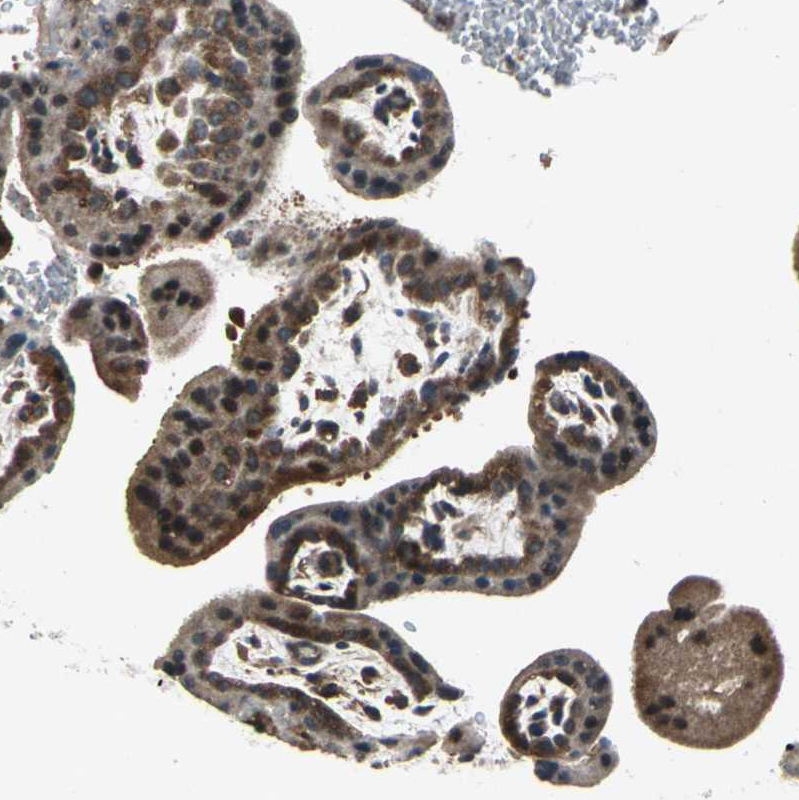

Immunohistochemistry analysis in human thyroid gland and liver tissues using HPA005841 antibody. Corresponding EIF2B2 RNA-seq data are presented for the same tissues.